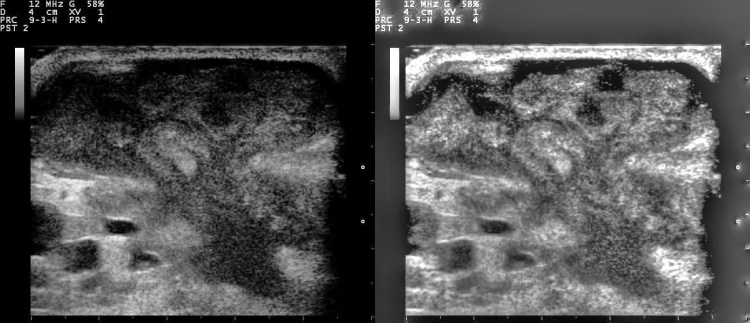

breast ultrasoundEl ultrasonido mamario es una herramienta invaluable en la detección y el diagnóstico de afecciones mamarias, pero ¿qué sucede si estás embarazada o amamantando? En este artículo, exploraremos la seguridad y la viabilidad de someterse a un ultrasonido mamario durante el embarazo o la lactancia.

Durante el embarazo, la salud y el bienestar tanto de la madre como del feto son de suma importancia. Afortunadamente, el ultrasonido mamario es considerado seguro durante el embarazo. Este procedimiento utiliza ondas sonoras de alta frecuencia para crear imágenes de los senos, sin emitir radiación ionizante que pueda representar un riesgo para el feto en desarrollo.